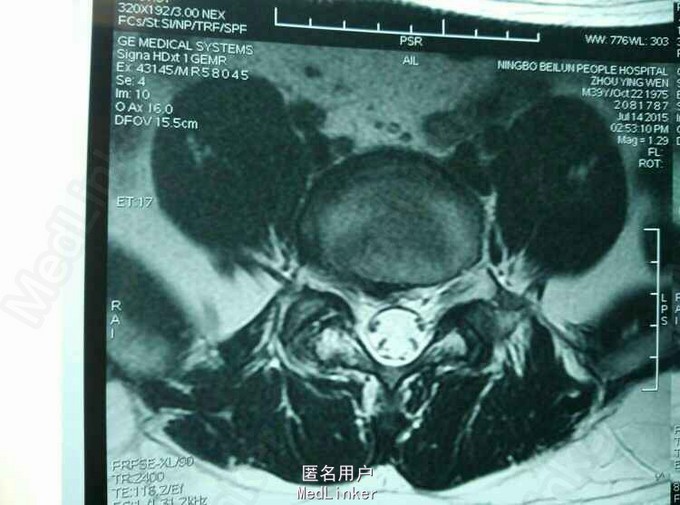

MRI及CT:L5S1 椎间盘脱出,向上游离。